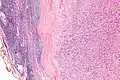

IPMs are diagnosed by examination of the tissue by a pathologist. They have a rim of peripheral lymphoid tissue (remnant of a lymph node) and consist of spindle cells with nuclear palisading. Red blood cell extravasation is common and blood vessels surrounded by collagen with (fine) peripheral spokes (amianthoid fibers) are usually seen.[2]

Immunostains for smooth muscle actin and cyclin D1 are characteristically positive. The main histologic differential diagnosis is schwannoma.

High mag.